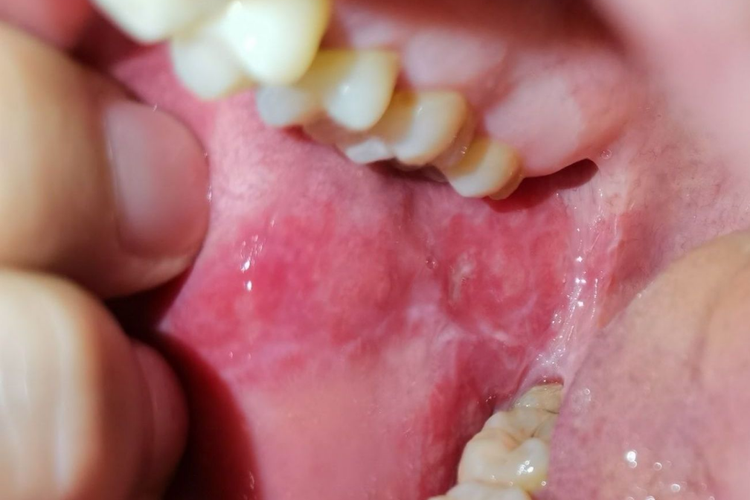

颊白线:位于双颊部与双侧后牙咬合线相对应的黏膜上,表现为连续的白色或灰白色线条,与牙列外形相吻合,呈水平状纵向延伸,明显高出黏膜面,光滑;在成年人中常见,一般无自觉症状。

口腔扁平苔藓:表现为小丘疹连成的线状白色或灰白色条纹(或花纹),类似皮肤损害的威肯姆线。白色花纹呈网状、树枝状、环状或半环状,黏膜可发生红斑、充血、糜烂、溃疡、萎缩和水疱等。患者自觉黏膜粗糙、木涩感、烧灼感、口干、偶有虫爬痒感。黏膜充血糜烂时,遇辛辣、热、酸、咸味刺激时,局部敏感灼痛。